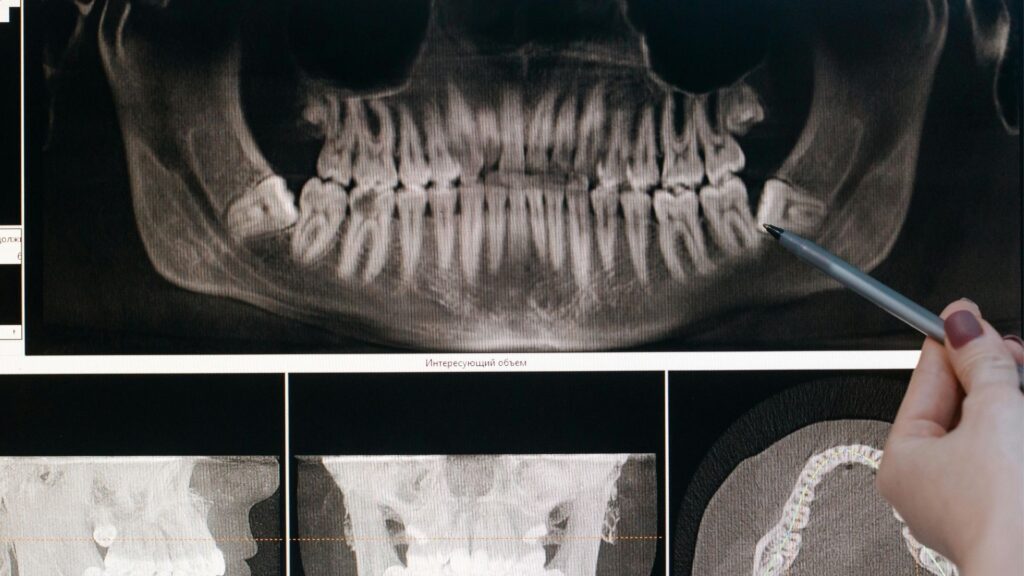

Az elrendelt bölcsességfog eltávolítás előtt a szakemberek panoráma röntgennel vagy szükség esetén CBCT-vel vizsgálják meg a pontos helyzetet. Az eljárás történhet egyszerű foghúzással, ha a fog kellőképpen előtört, vagy szájsebészeti beavatkozással, amennyiben csak részben vagy egyáltalán nem látható a fogkorona. A beavatkozás általában helyi érzéstelenítésben történik, de igény esetén altatásban is elvégezhető a páciens komfortérzete érdekében. A megfelelő utógondozás és a fogorvosi utasítások betartása elengedhetetlen a szövődménymentes gyógyuláshoz.

A rendelőben nagy hangsúlyt fektetnek a fájdalommentes kezelésekre, melyeket helyi érzéstelenítésben vagy igény szerint altatásban végeznek. A pontos diagnózist modern diagnosztikai eszközök, mint a fogászati CT és panorámaröntgen segítik. Az All-on-4 implantációs eljárás, a rögzített fogsor, valamint a különböző koronatípusok (cirkon, préskerámia) mind a páciensek egyéni igényeihez illeszkedő megoldásokat kínálnak. A korszerű eszközök és a legjobb minőségű fogászati anyagok használata biztosítja, hogy a beavatkozások hosszú távon is megbízható eredményt nyújtsanak.